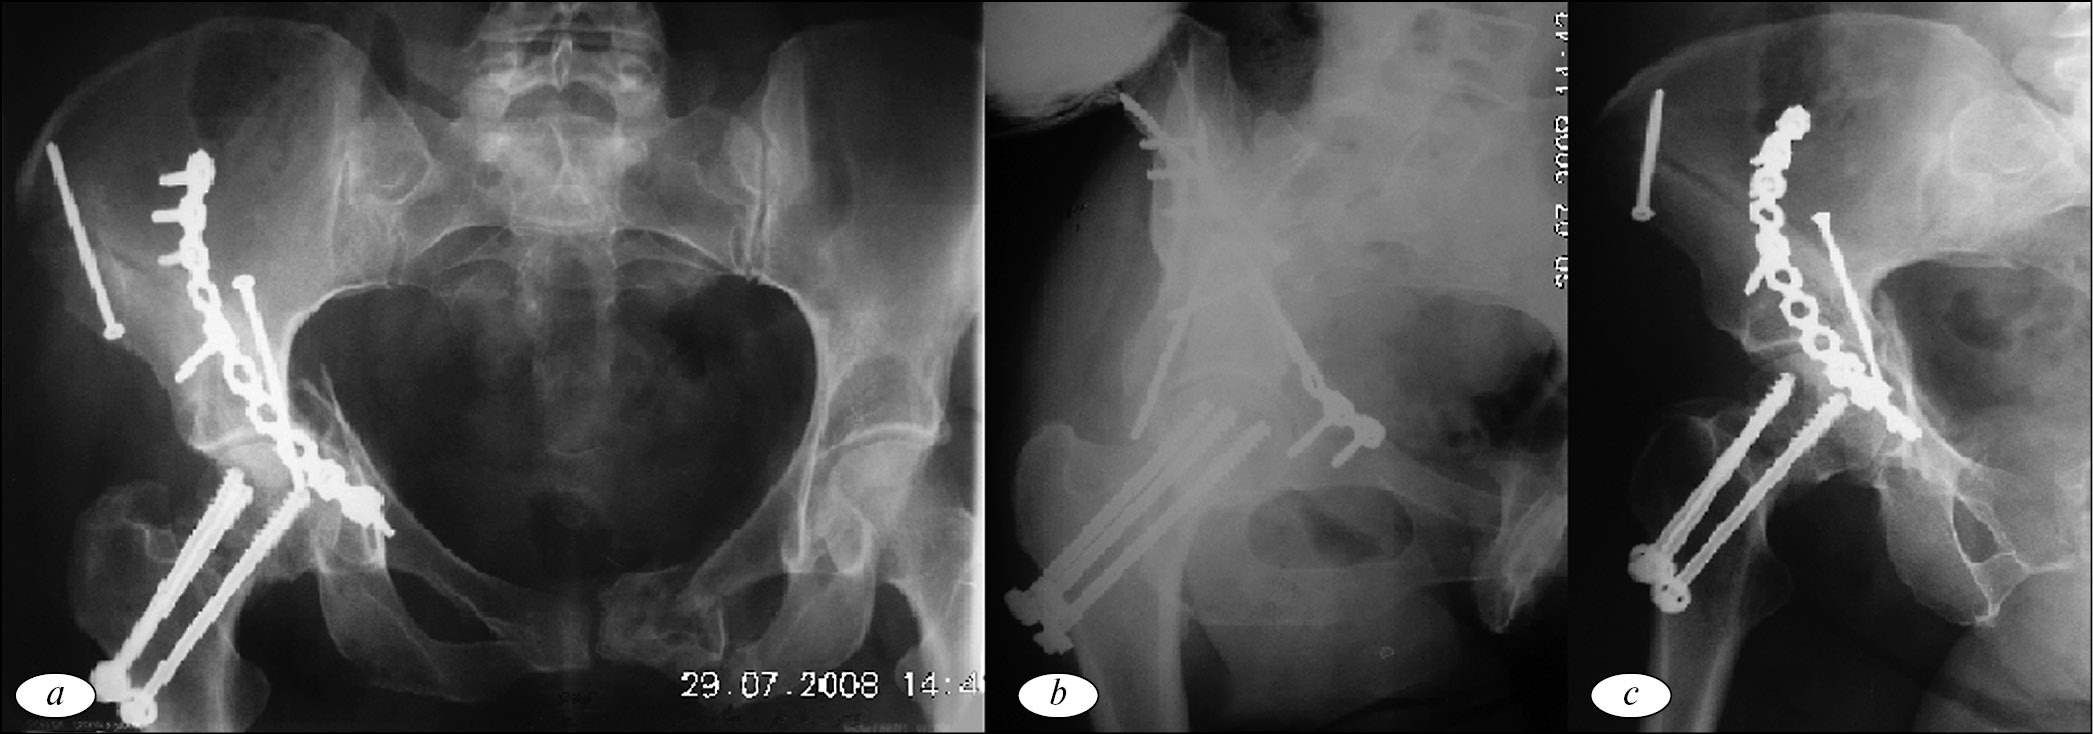

Начата инфузионная терапия. Учитывая невозможность наложения аппарата первичной фиксации по причине значительного разрушения правой подвздошной кости, принято решение фиксировать место повреждения методом скелетного вытяжения. Пациентка госпитализирована в отделение реанимации. После компенсации общего состояния на третьи сутки после травмы больная переведена в профильное отделение. В отделении проводилось симптоматическая терапия, лечебная физкультура, применялись антикоагулянты, скелетное вытяжение. В обязательном порядке, в плане предоперационной подготовки, выполнена полипроекционная рентгенография правой вертлужной впадины и компьютерная томография тазобедренного сустава (рис. 1).

Рис. 1. Рентгенограммы пациентки Б. в прямой (а), запирательной (b), подвздошной (c) проекциях, компьютерная томограмма правого тазобедренного сустава (d)